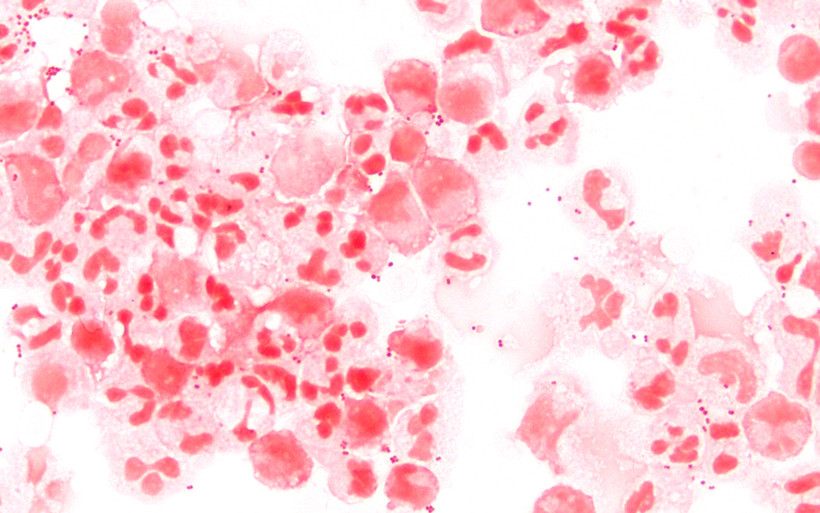

Vi khuẩn Neisseria meningitidis. (Nguồn: Wikipedia)

Bác sỹ Trần Văn Tuyến, Phó Giám đốc Sở Y tế Bắc Kạn cho biết kết quả xét nghiệm của Bệnh viện Bệnh nhiệt đới Trung ương ngày 12/6 cho thấy, bệnh nhân Đ.V.D (là con trai bà H.T.Đ) dương tính với vi khuẩn não mô cầu (có tên gọi là Neisseria meningitidis) gây bệnh viêm màng não.